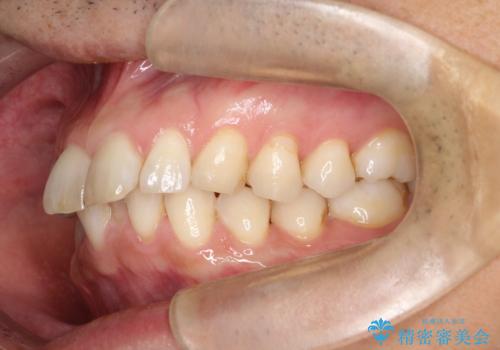

【インザライン】前歯の凸凹を治したい

- 前歯の凸凹を主訴に来院されました。

下顎位が右方に変異しており、外科矯正も提案しましたが患者様は希望されず、インビザラインにて治療を完了しております。

叢生のスペースを確保するために、臼歯部の遠心移動を行っています。

今回の治療計画は上顎の正中を顔と揃えることを優先しています。